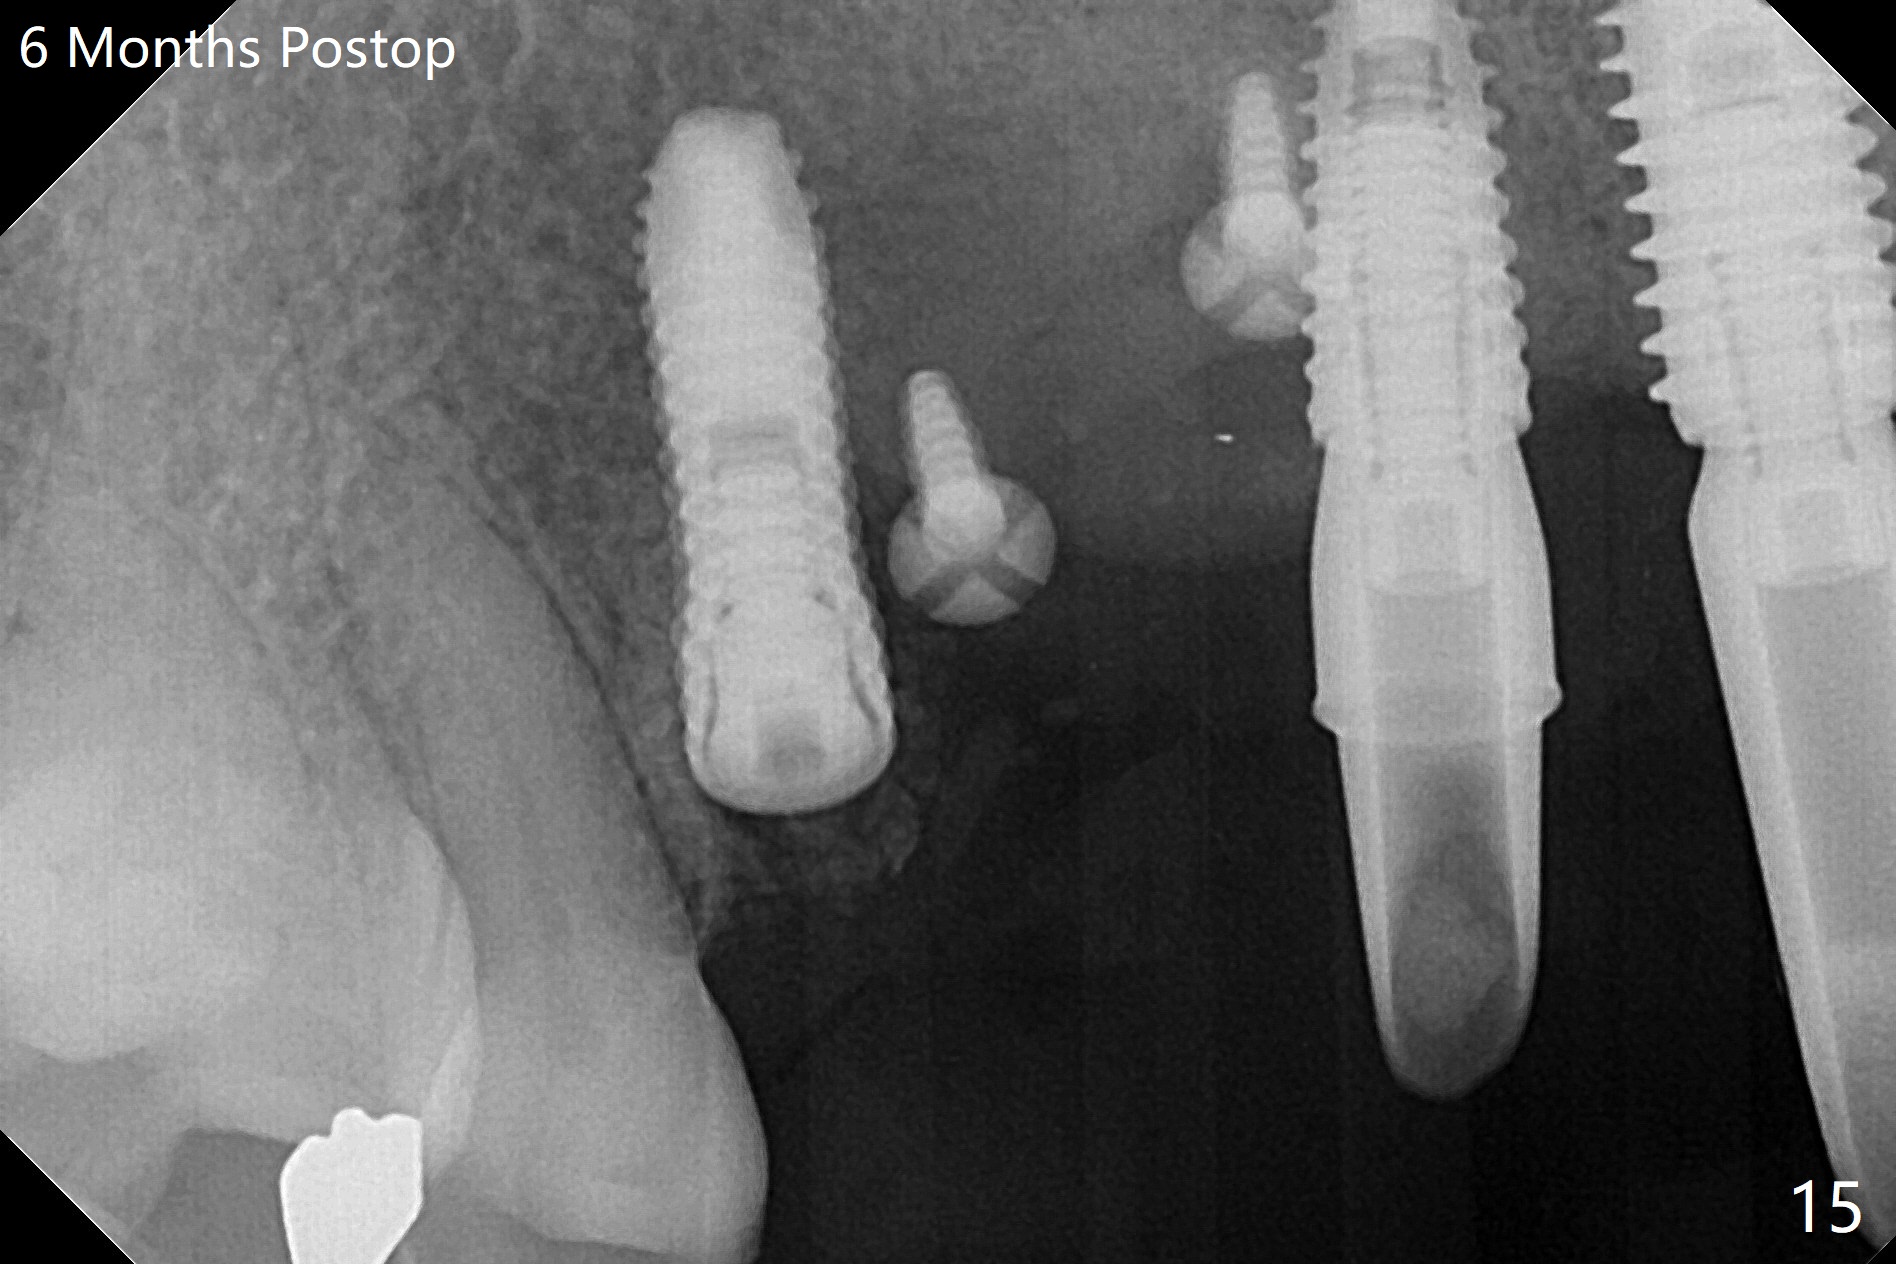

在6,7号牙位牙槽嵴切口,翻瓣,找不到上次放置的tenting screw,不过7号牙位骨质虽然低,够宽的,开始钻洞(图四),植入3.8乘8.5毫米植体,扭力足够(图五),近中舌侧暴露螺纹堆加骨粉(图五*),然后放置基台,再次在后者周围放置骨粉(图五至七),覆盖两张PRF膜后缝合(图八),最后在三个箭头周围放置牙周敷料。术后CT显示植体与tenting screws(图九,十箭头)有一定距离,但是5号牙植体颊侧根尖穿孔(图九 *)。如果植体不脱落,需做侧方切口植骨。术后七天7号植体腭侧肿胀(图十一 *),切开没有脓水,插入牙胶尖,它末端指向7号植体周围tenting screw。后者可能需要拔除,同时5号牙颊侧根尖植骨,但是为时太早,可能打搅骨粉生长。术后两周腭侧肿胀没有消失,但是不痛,继续观察。术后接近6个月,软组织正常(图十三),但是5,7植体周围没有骨质(图十四,五)。由于近中tenting screws周围软组织触痛(局麻不全情况下),螺钉取出(图十六,七(*)),而远中螺钉好像有帮助5植体螺纹骨粉撑起,所以留下(腭侧穿孔部分去除),最后放置粘性骨粉(图十八:*)和PRF膜(两张由7基台打孔固定)。